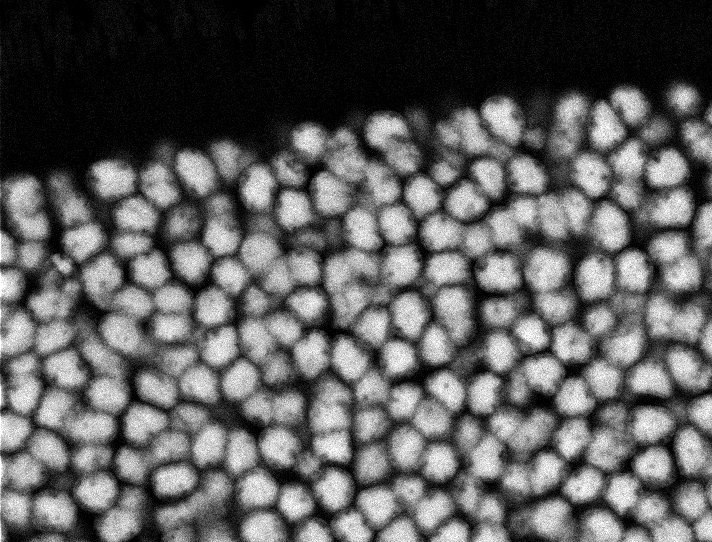

Healthy Retina

Unhealthy Retina